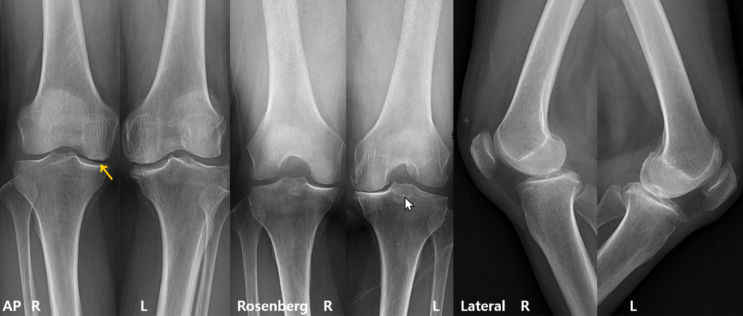

[무릎] SIF Subchondral insufficiency fracture 연골하 불충분 골절

[증례] F/70 2개월전 , 갑자기, 우측 무릎 통증 시작 걷기 힘듬 / 1주전 계단 내려갈때 뚝 소리 나더니 악...